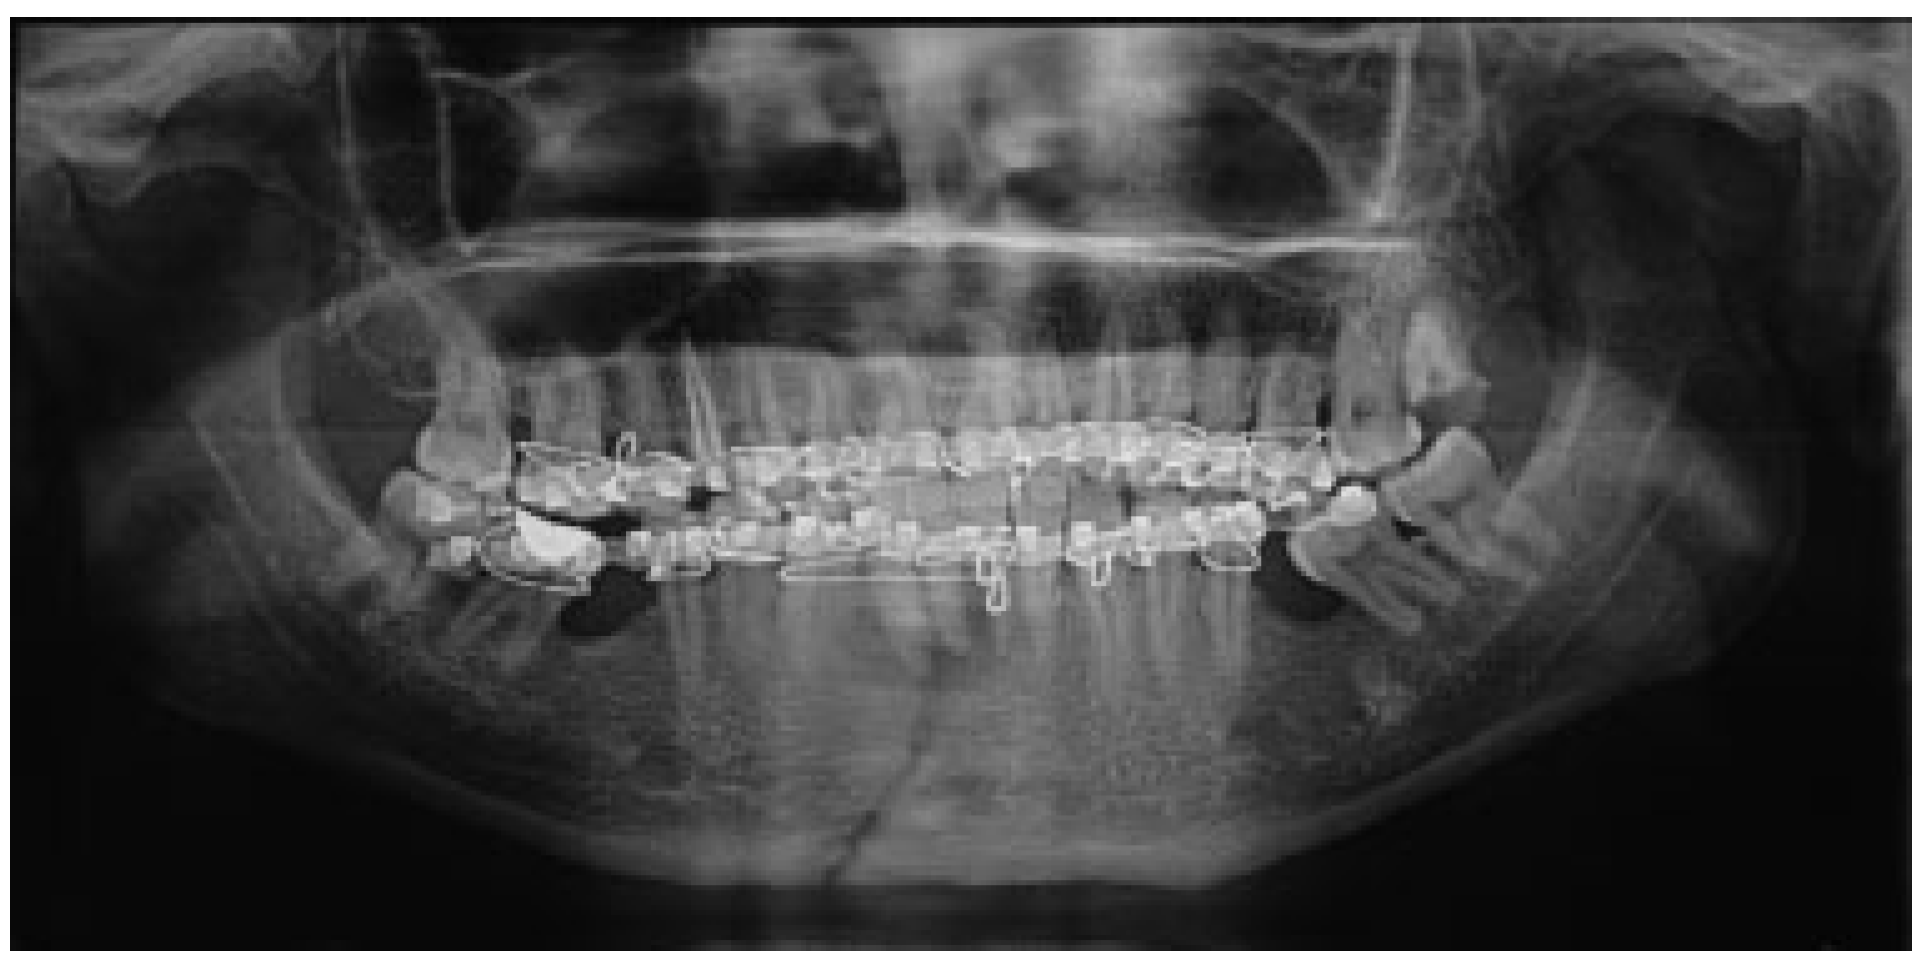

The mean for ramal height shortening was found to be 11.9 (0.99) preoperatively and 11.6 (1.57) postoperatively in Group A. It was compared using paired t-test and this difference was found not to be statistically significant (p = 0.34; Figure 1 and Figure 2). The mean for ramal height shortening was found to be 12.5 (0.84) preoperatively and (0.87) postoperatively in Group B. It was compared using paired t-test and this difference was found to be statistically significant (p < 0.05; Figure 3 and Figure 4).

Figure 3.

Group B: Preoperative orthopantomography showing left displaced subcondylar fracture and right parasymphysis fracture.

Figure 4.

Group B: Postoperative orthopantomography.

The mean for fracture displacement was found to be 29.9 (4.67) preoperatively and 28.2 (5.67) postoperatively in Group A. It was compared using paired t-test and this difference was found not to be statistically significant (p < 0.34). The mean for fracture displacement was found to be 30.9 (3.14) preoperatively and 1.8 (1.47) postoperatively in Group B. It was compared using paired t-test and this difference was found to be statistically significant (p < 0.05; Table 2).